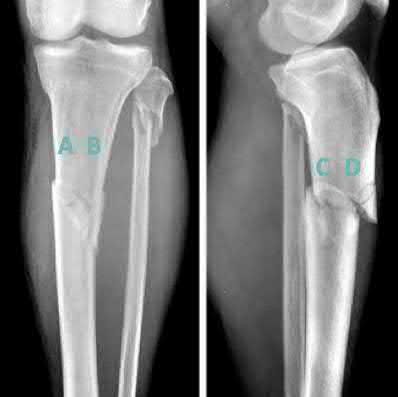

A 28-year-old male sustains a closed comminuted tibial shaft fracture.

Two hours post-injury, he develops severe leg pain unyielding to narcotics. His blood pressure is 120/80 mmHg. Intracompartmental pressure monitoring is performed. Based on current guidelines, which measurement dictates an emergent 4-compartment fasciotomy?

Explanation

Acute compartment syndrome is classically defined by tissue hypoperfusion. The absolute compartment pressure is less reliable than the differential pressure (Delta P). A Delta P (Diastolic Blood Pressure minus Compartment Pressure) of less than 30 mmHg is an absolute indication for emergency fasciotomy, as capillary perfusion gradient is lost when tissue pressure approaches the diastolic pressure.